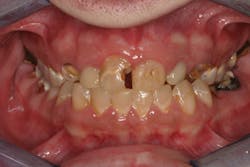

For example, one patient of a general dental practice had a caries-free history for 35 years. He ceased smoking traditional cigarettes and decided to vape as he thought this was a healthier alternative. Within a year, cervical enamel demineralization and interproximal lesions were present on the mandibular anterior sextant, consistent with the primary point of contact of the e-liquid aerosol (figure 2).

Figure 3: Effects of e-cigarettes